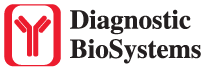

Solitary fibrous tumor (SFT) is a fibroblastic neoplasm of variable biologic potential that can arise at a wide range of anatomic sites. Almost all cases of (98%) including conventional, cellular, atypical, and malignant variants showed nuclear expression of STAT6. Staining for STAT6 was usually diffuse: 68% of cases showed reactivity for STAT6 in 75% of tumor cells. Further, the intensity of staining was strong in 67% of cases, moderate in 25%, and weak in only 7%. The heterogeneity of staining, both in terms of extent and intensity, which may be because of uneven tissue fixation or loss of antigenicity in older cases for which the unstained slides were stored for extended periods of time. All other tumor types examined were negative for STAT6, except for three dedifferentiated liposarcomas and one deep fibrous histiocytoma, which showed weak staining. STAT6 is therefore a highly sensitive and almost perfectly specific immunohistochemical marker for SFT, and can be helpful to distinguish this tumor type from histologic mimics.

| Positive Control Tissue | Solitary fibrous tumor |